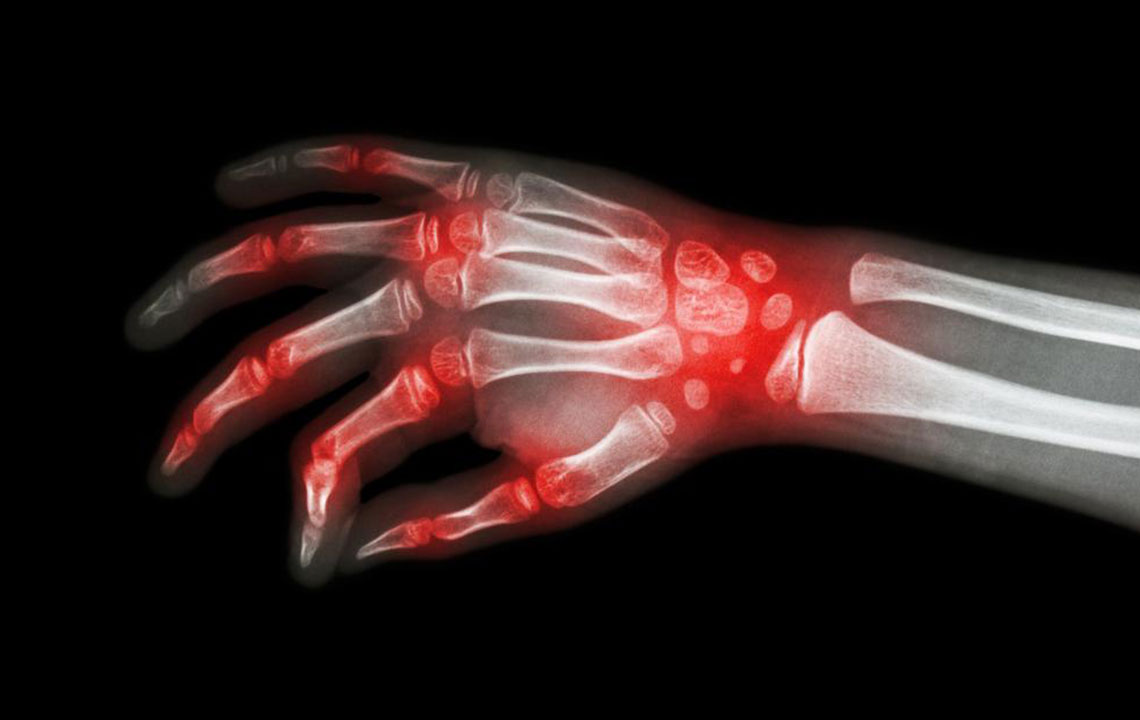

Rheumatoid arthritis and lupus – what makes them similar?

Lupus and rheumatoid arthritis are both autoimmune conditions that are often confused to be the same. The fact that these – rheumatoid arthritis, lupus are autoimmune diseases makes their symptoms similar too. Auto immune diseases are typically those conditions where the immune system of the body attacks healthy cells, causing inflammation, swelling, and pain in the affected areas.